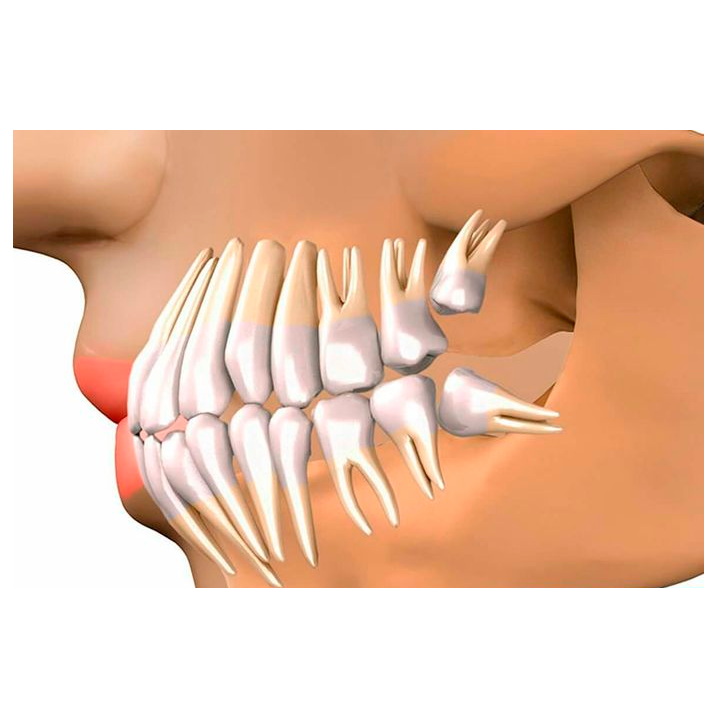

- Ver expedienteCirugía de 3os Molares